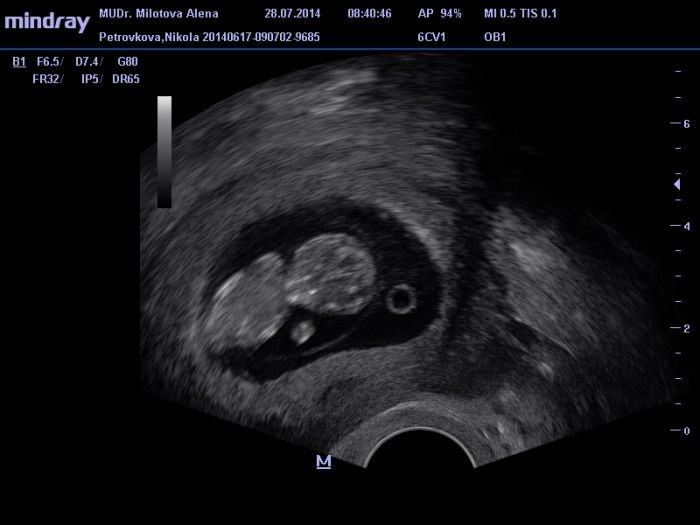

Ahoj holky :) Adrus jsem rada ze uz je to leepsi u me uz taky super, nezvracim a cejtim se fajn :) vzdycky mam tak dva dny pokoj a pak jen zaludek na vode trosicku :)... Jinak teda ja mam nahore 5 kilo :D dnes jsem se vazila u doktorky a malem jsem upadla kdyz jsem to videla nechapu to nejim a bylo mi furt blbe :D a 5 kilo :D pritel prej ze to ani neni videt na me ale nevim teda :D musim najit nejake cviceni pro tehulky a zacit cvicit taky.. Jinak kontrola dopadla dobre :) dostala jsem prukazku, brali mi krve (5 ampuli) a na screening jdu 11.8. :) a pak na dalsi ko 18.8. ... Tak doufam ze bude vse v poradku a mrnousek bude zdravej a vecne vysmatej po mamince...:) Dokonce ted zjistuju ze mi je fakt uplne fuk co to vlasne bude, tak jak jsem chtela kluka tak mi to je ted opravdu jedno :) .. Jinak hormony pracujou ... Jsem naladovka a taky umim kraasne brecet kdyz vidim miminko nejake atak :D .. posilam par fotek z dnesniho utz :)

[602466] Nikol,gratuluji k úspěšně kontrole a taky už Ti bude líp.foto je krásne.tak to ti brali hodně ampuli,mne jen 3.a na screening jdu teď ve středu,krev i utz naráz.a další kontrola 13.8.teď snad už bude mě mít všechny jen pozitivní zprávy.